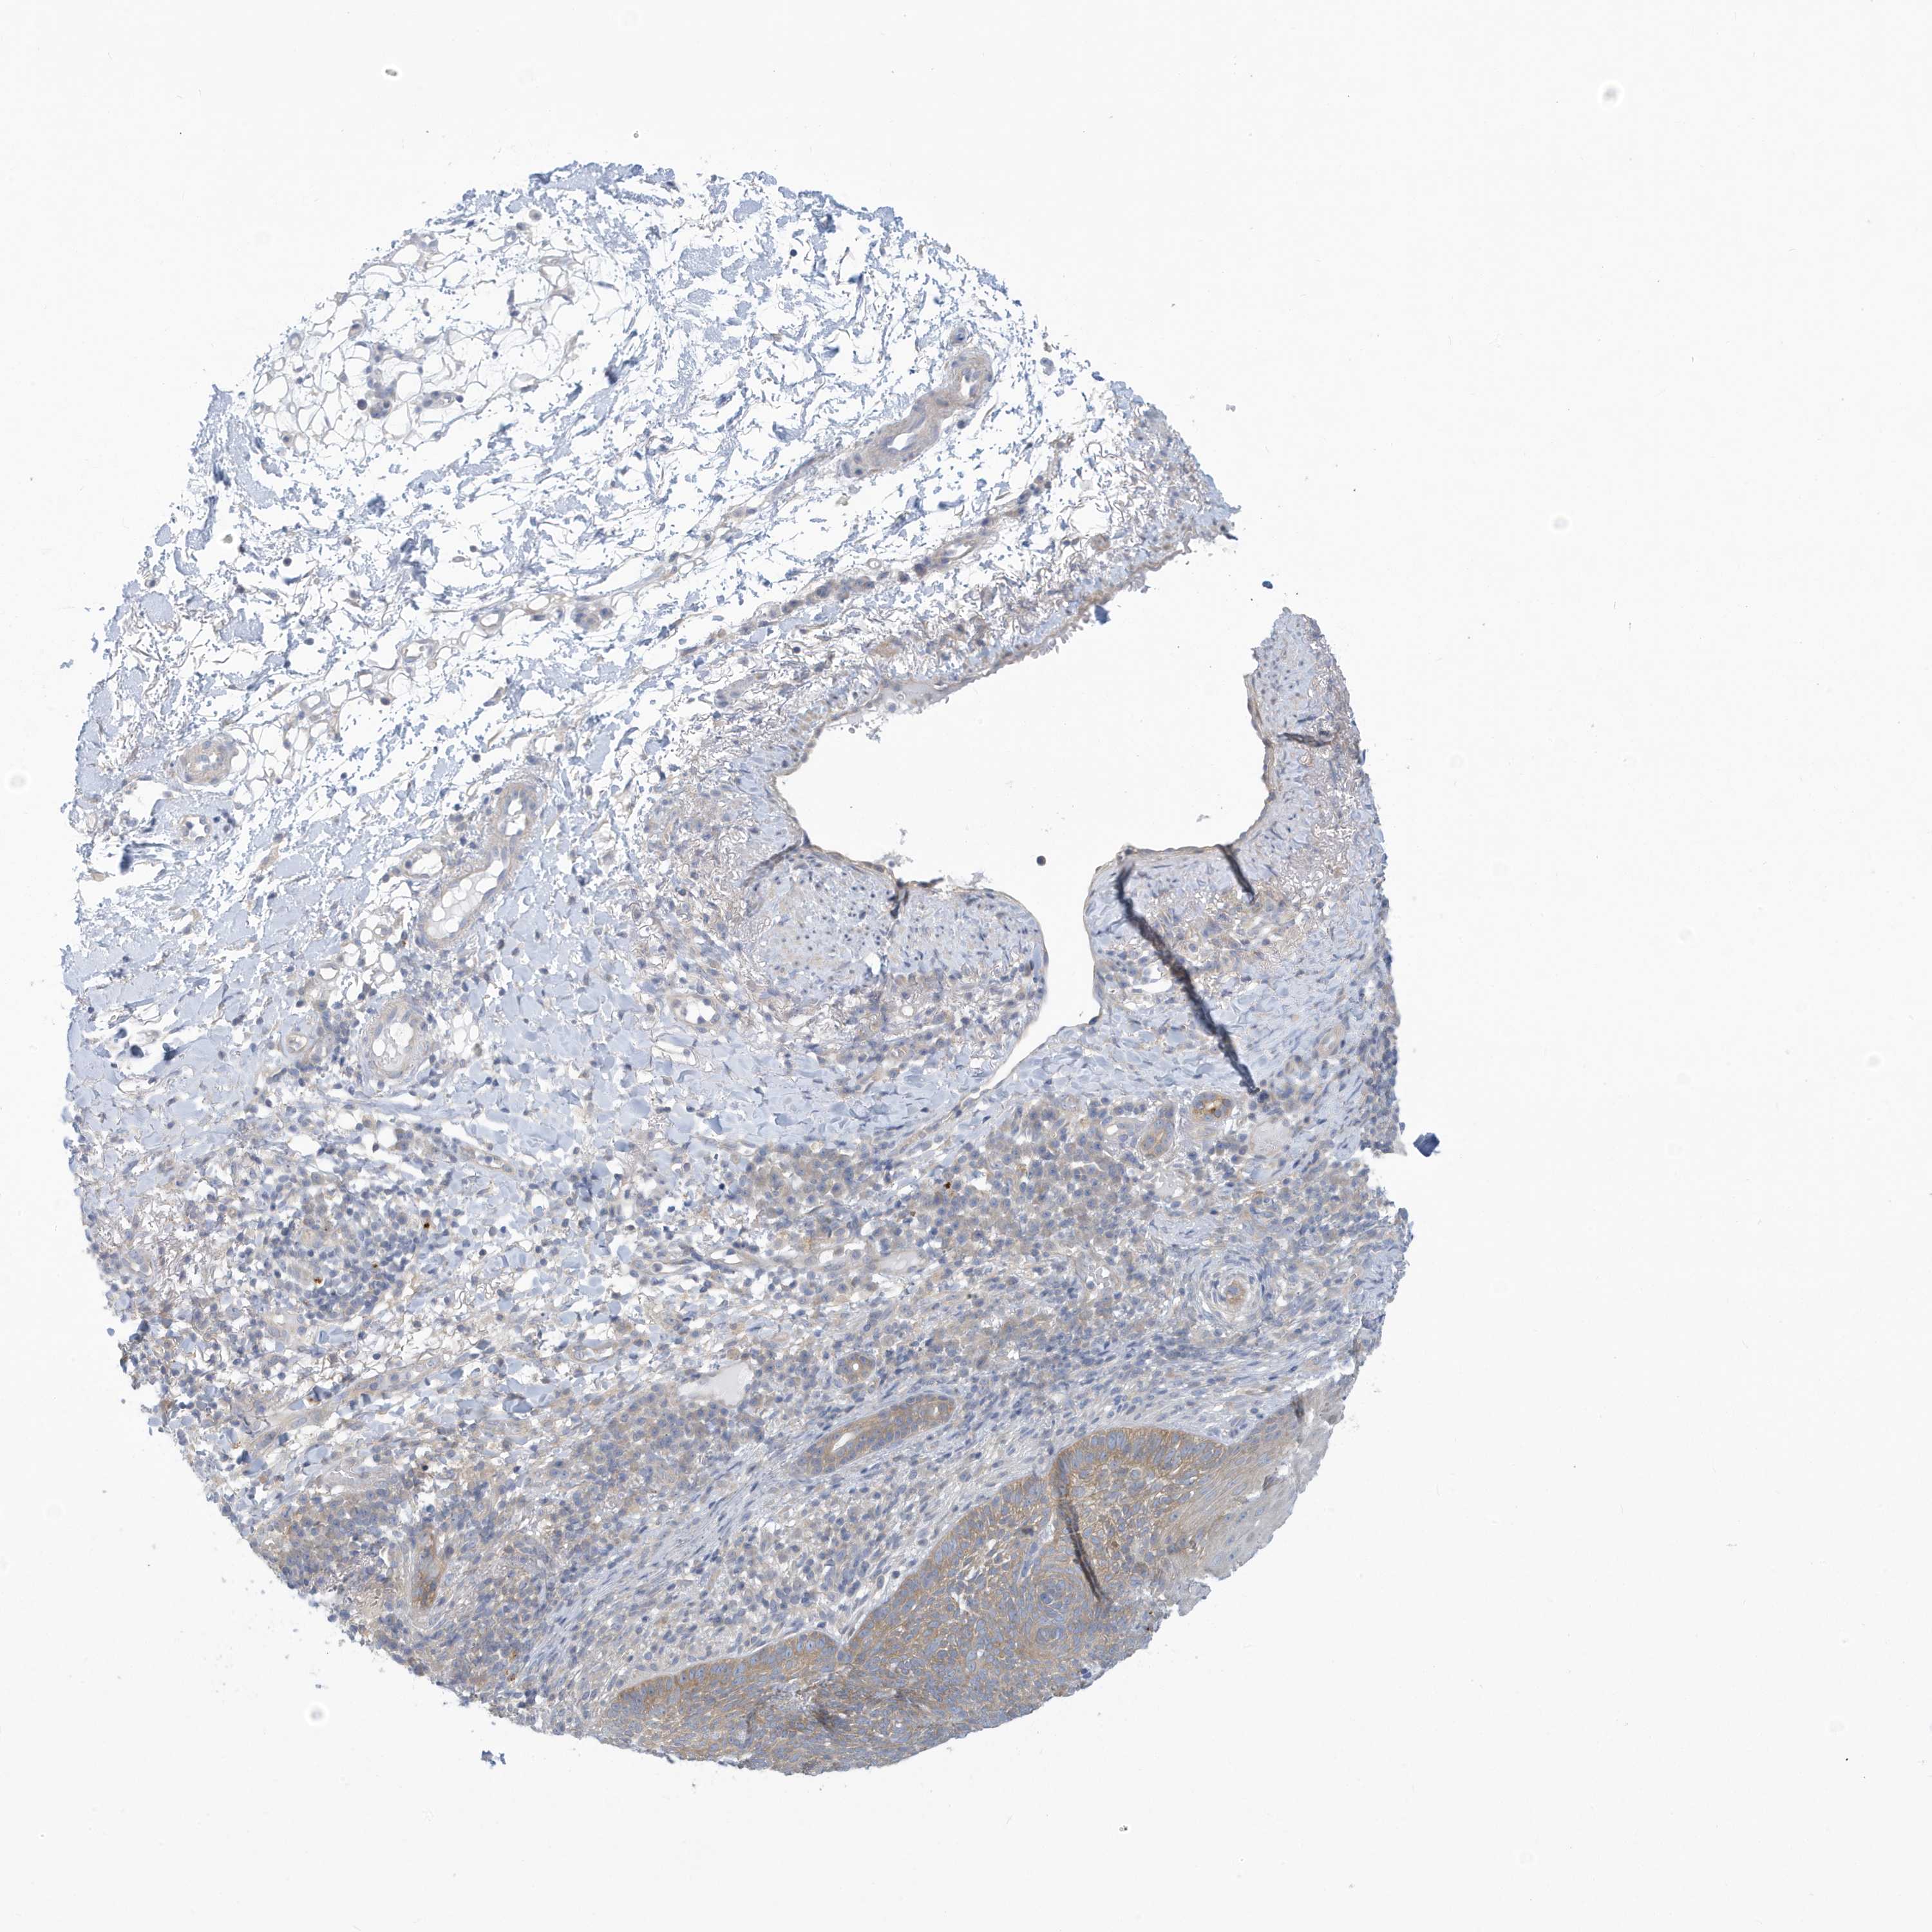

Basal cell and squamous cell cancer

SKIN CANCER - Protein expressioni

A mouse-over function shows sample information and annotation data. Click on an image to view it in a full screen mode. Samples can be filtered based on level of antibody staining by selecting one or several of the following categories: high, medium, low and not detected. The assay and annotation is described here.

Each image is clickable and will lead to virtual microscopy that enables deeper exploration of all samples and also displays staining intensity scores, fraction scores and subcellular localization as well as patient and tissue information for each sample.

Antibody HPA030968

Staining

High

Medium

Low

Not detected

Intensity

Strong

Moderate

Weak

Negative

Quantity

>75%

75%-25%

<25%

None

Location

Nuclear

Cytoplasmic/membranous

Cytoplasmic/membranous,nuclear

Squamous cell carcinoma, NOS